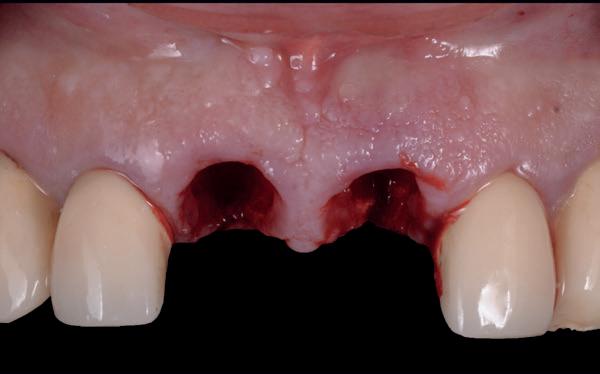

Het kantelpunt: de patiënt komt terug (afbeelding 14-16)

De patiënt meldde zich opnieuw in de praktijk met klachten: pijn, zwelling en een duidelijke intraorale infectie. Bij inspectie zag ik direct een probleemhet ging om een klassiek beeld van peri-implantair botverlies met een abces. Dit patroon van botverlies en infectie spiegelde sterk de gevolgen van thermische trauma.

Op de röntgenfoto’s zag ik wat ik al vreesde: er was botresorptie rond het implantaat. De zachte weefsels waren ontstoken en het implantaat vertoonde teke-

nen van mobiliteit. Op dat moment wist ik precies wat er was misgegaan.

Dit was geen kwestie van een verkeerde occlusie of een slecht gekozen abutment. Dit was een puur biologisch probleem, veroorzaakt door mijn onderpreparatie van de osteotomie en de daarmee gepaard gaande botnecrose of compressie. Mijn streven naar immediaat belasten had me verblind, en ik had een fundamentele regel van de implantologie genegeerd: bot moet kunnen ademen. Op dat moment had ik geen andere keuze dan de situatie te herstellen.

Herstel: terug naar de basis (afbeelding 17-19)

De behandeling van dit mislukte implantaat volgde een stapsgewijze aanpak:

1. Explantatie van het implantaat. Het implantaat werd voorzichtig verwijderd, waarbij ik probeerde zoveel mogelijk bot te behouden.

2. Curettage en reiniging. De alveole werd intensief gecuretteerd en gespoeld tot er geen exsudaat meer aanwezig was. Met goede communicatie kon ik de patiënt overtuigen om 3 maanden later terug te komen voor de botopbouw, zodat we het beste fundament konden creëren voor een duurzame oplossing.

3. Botopbouw met GBR. Ik koos voor een combinatie van allograft, xenograft en autograft om de botdeficiëntie aan te pakken. Dit mixen van bottypes creëerde een optimale omgeving voor regeneratie.

4. Twee-fasen implantologie. Dit keer nam ik geen risico’s. In plaats van een immediaat implantaat koos ik voor een delayed plaatsing. Het bot kreeg eerst de tijd om te rijpen voordat ik een nieuw implantaat plaatste. Deze keer verliep de procedure zonder problemen. Het bot herstelde zich zoals verwacht en na enkele maanden kon ik een nieuw implantaat plaatsen, met een correcte osteotomie en zonder onnodige compressie.